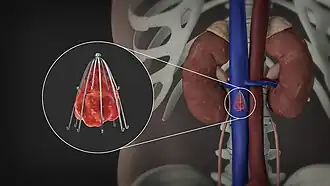

Inferior vena cava filter

Inferior vena cava filter - Gunther Tulip.[1] | |

An inferior vena cava filter is a medical device made of metal that is implanted by vascular surgeons or interventional radiologists into the inferior vena cava to prevent a life-threatening pulmonary embolism (PE) or venous thromboembolism (VTE).[2][3]

The filter is designed to trap a blood clot and prevent its travel to the lung where it would form a pulmonary embolism.[4][3] Their effectiveness and safety profile is well established, and they may be used when anticoagulant treatment is not sufficient.[5]

IVC filters are placed endovascularly, meaning that they are inserted via the blood vessels. Historically, IVC filters were placed surgically, but with modern filters that can be compressed into much thinner catheters, access to the venous system can be obtained via the femoral vein (the large vein in the groin), the internal jugular vein (the large vein in the neck) or the arm veins with one design. Choice of route depends mainly on the number and location of any blood clot within the venous system. To place the filter, a catheter is guided into the IVC using fluoroscopic guidance, then the filter is pushed through the catheter and deployed into the desired location, usually just below the junction of the IVC and the lowest renal vein.[44]